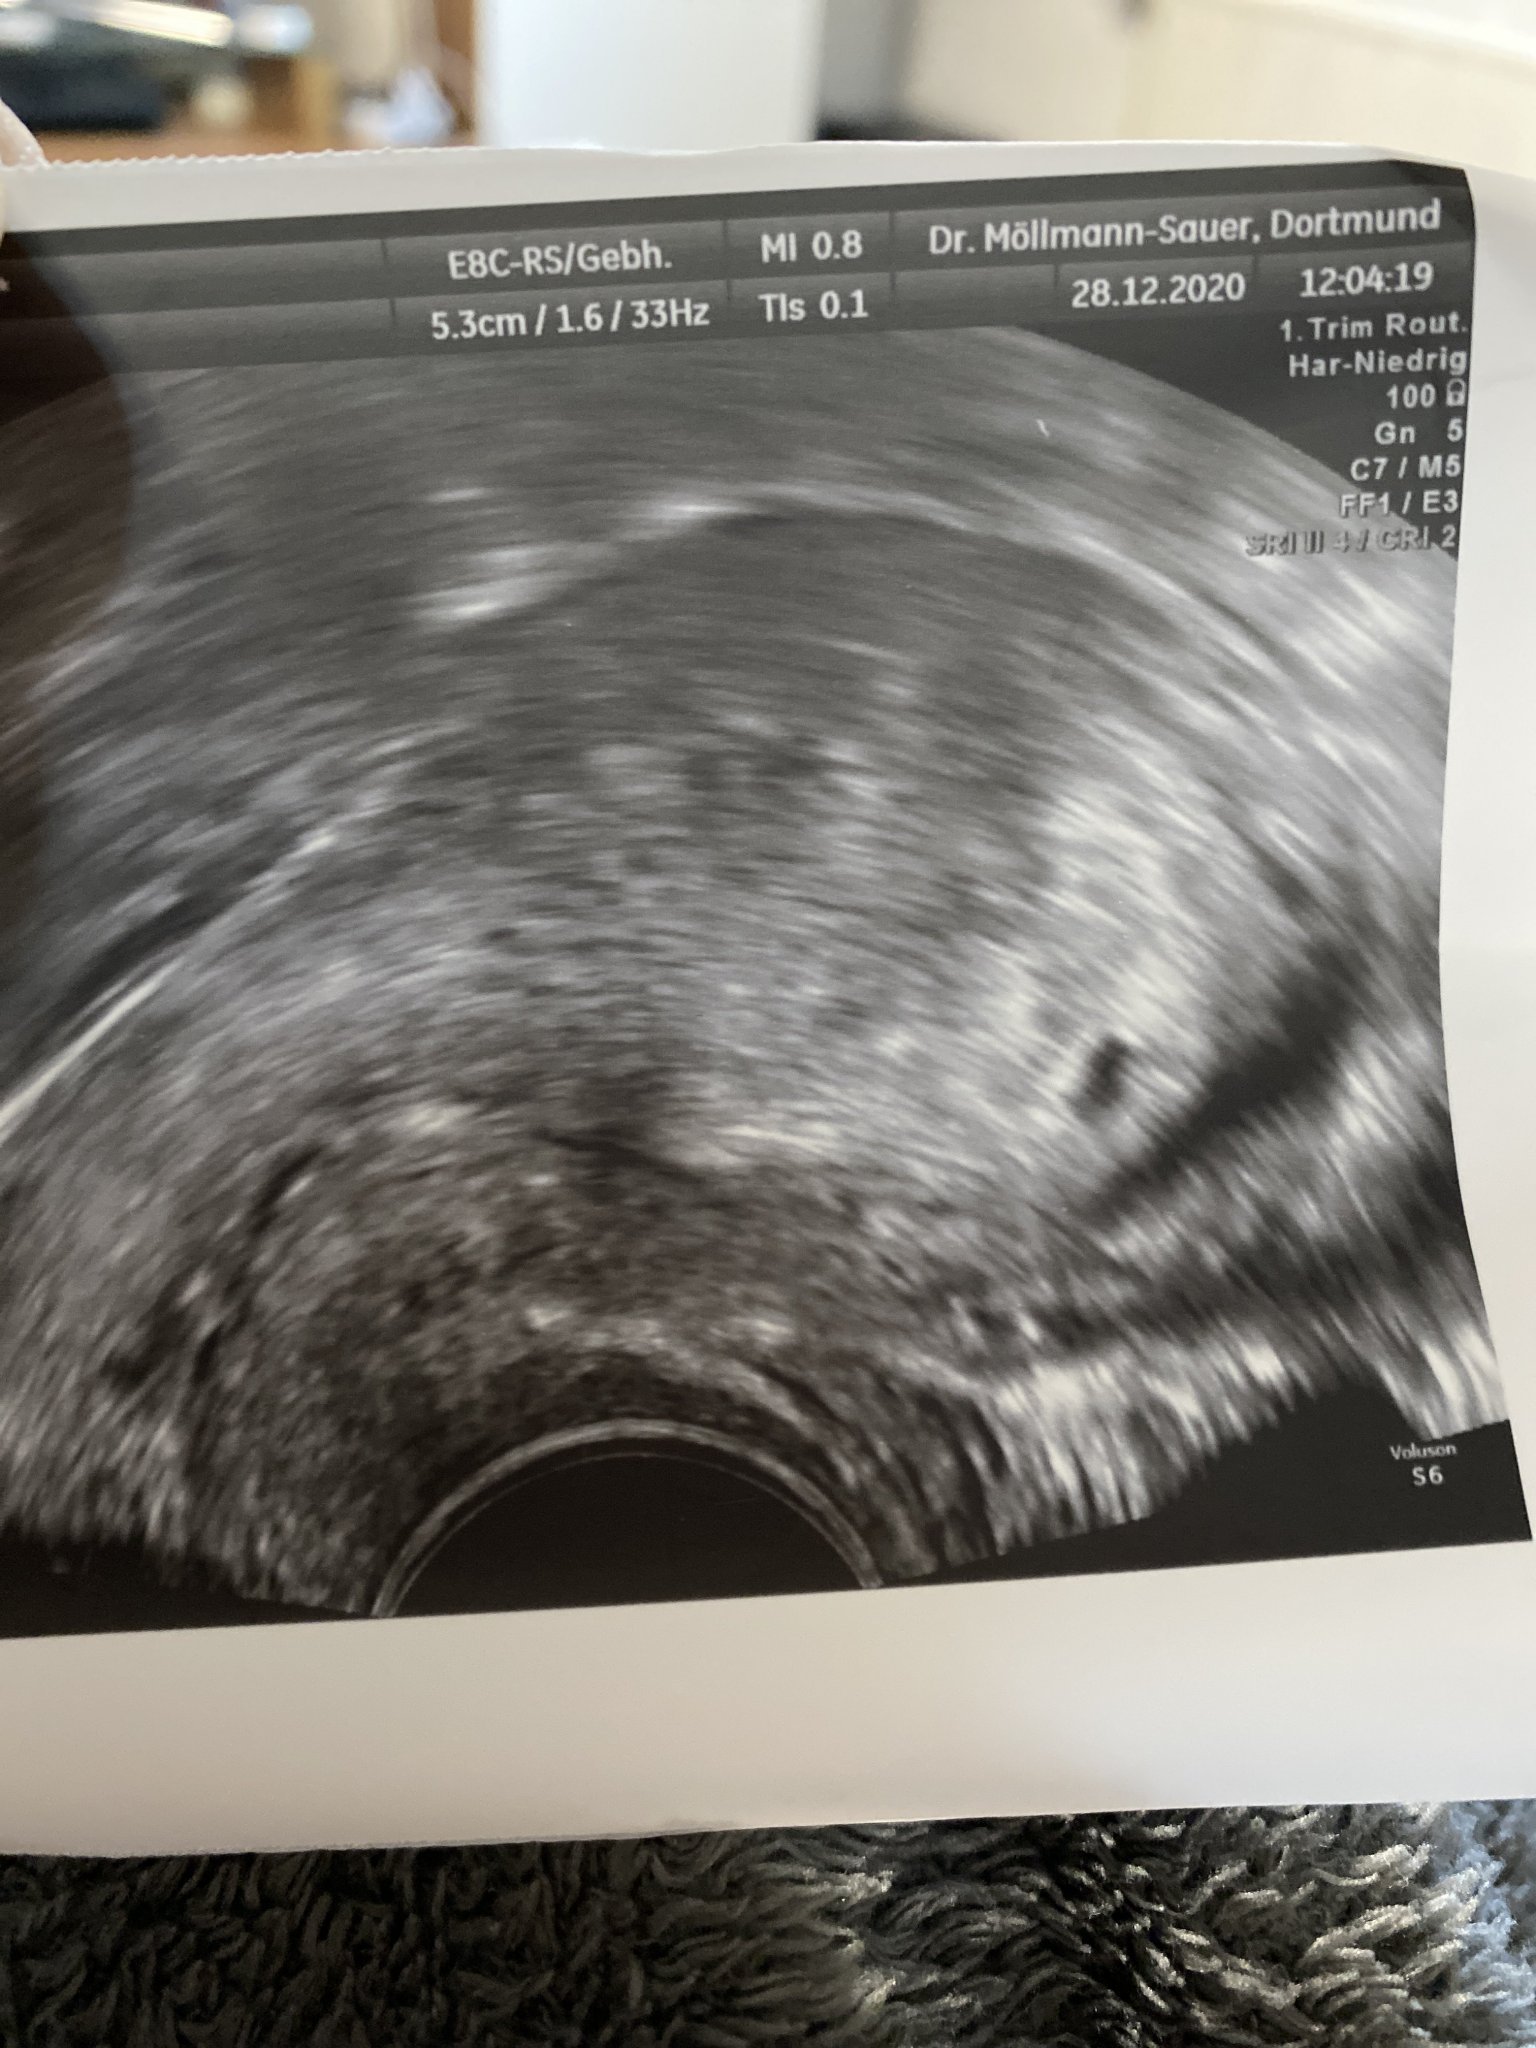

Здравейте.Пиша ви от името на една близка приятелка.

5 години не можеха да имат деца,но сега е с няколко положителни теста + преглед при гинеколог.Закъснява и с 9 дни(днес е била на преглед с вагинален ехограф!)но докторката бързо я е изпратила по живо,по здраво.Не е казала да пие фолиева киселина,нито седмица на бременност е казала,дори брменност не е потвърдила.С две думи нищо.Само една снимка и е дала и това е.Вижда се може би плоден сак,но точица не??Вие какво мислите, момичета?

Предишната и менструация е била на 20.11 ...